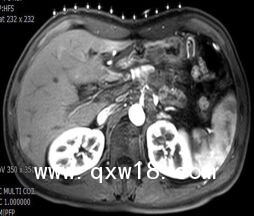

醫(yī)學(xué)圖像體外定位貼(MK#MR型,MR引導(dǎo)定位柵)產(chǎn)品說明:

【適用范圍】

MR引導(dǎo)下介入穿刺活檢或治療

【突出優(yōu)點(diǎn)】

為開展磁共振引導(dǎo)下穿刺活檢和消融介入治療創(chuàng)造了快捷定位條件??芍貜?fù)使用,全球獨(dú)有,多序列成像,標(biāo)記清晰。

【產(chǎn)品規(guī)格】

19cm×20cm,1套裝。